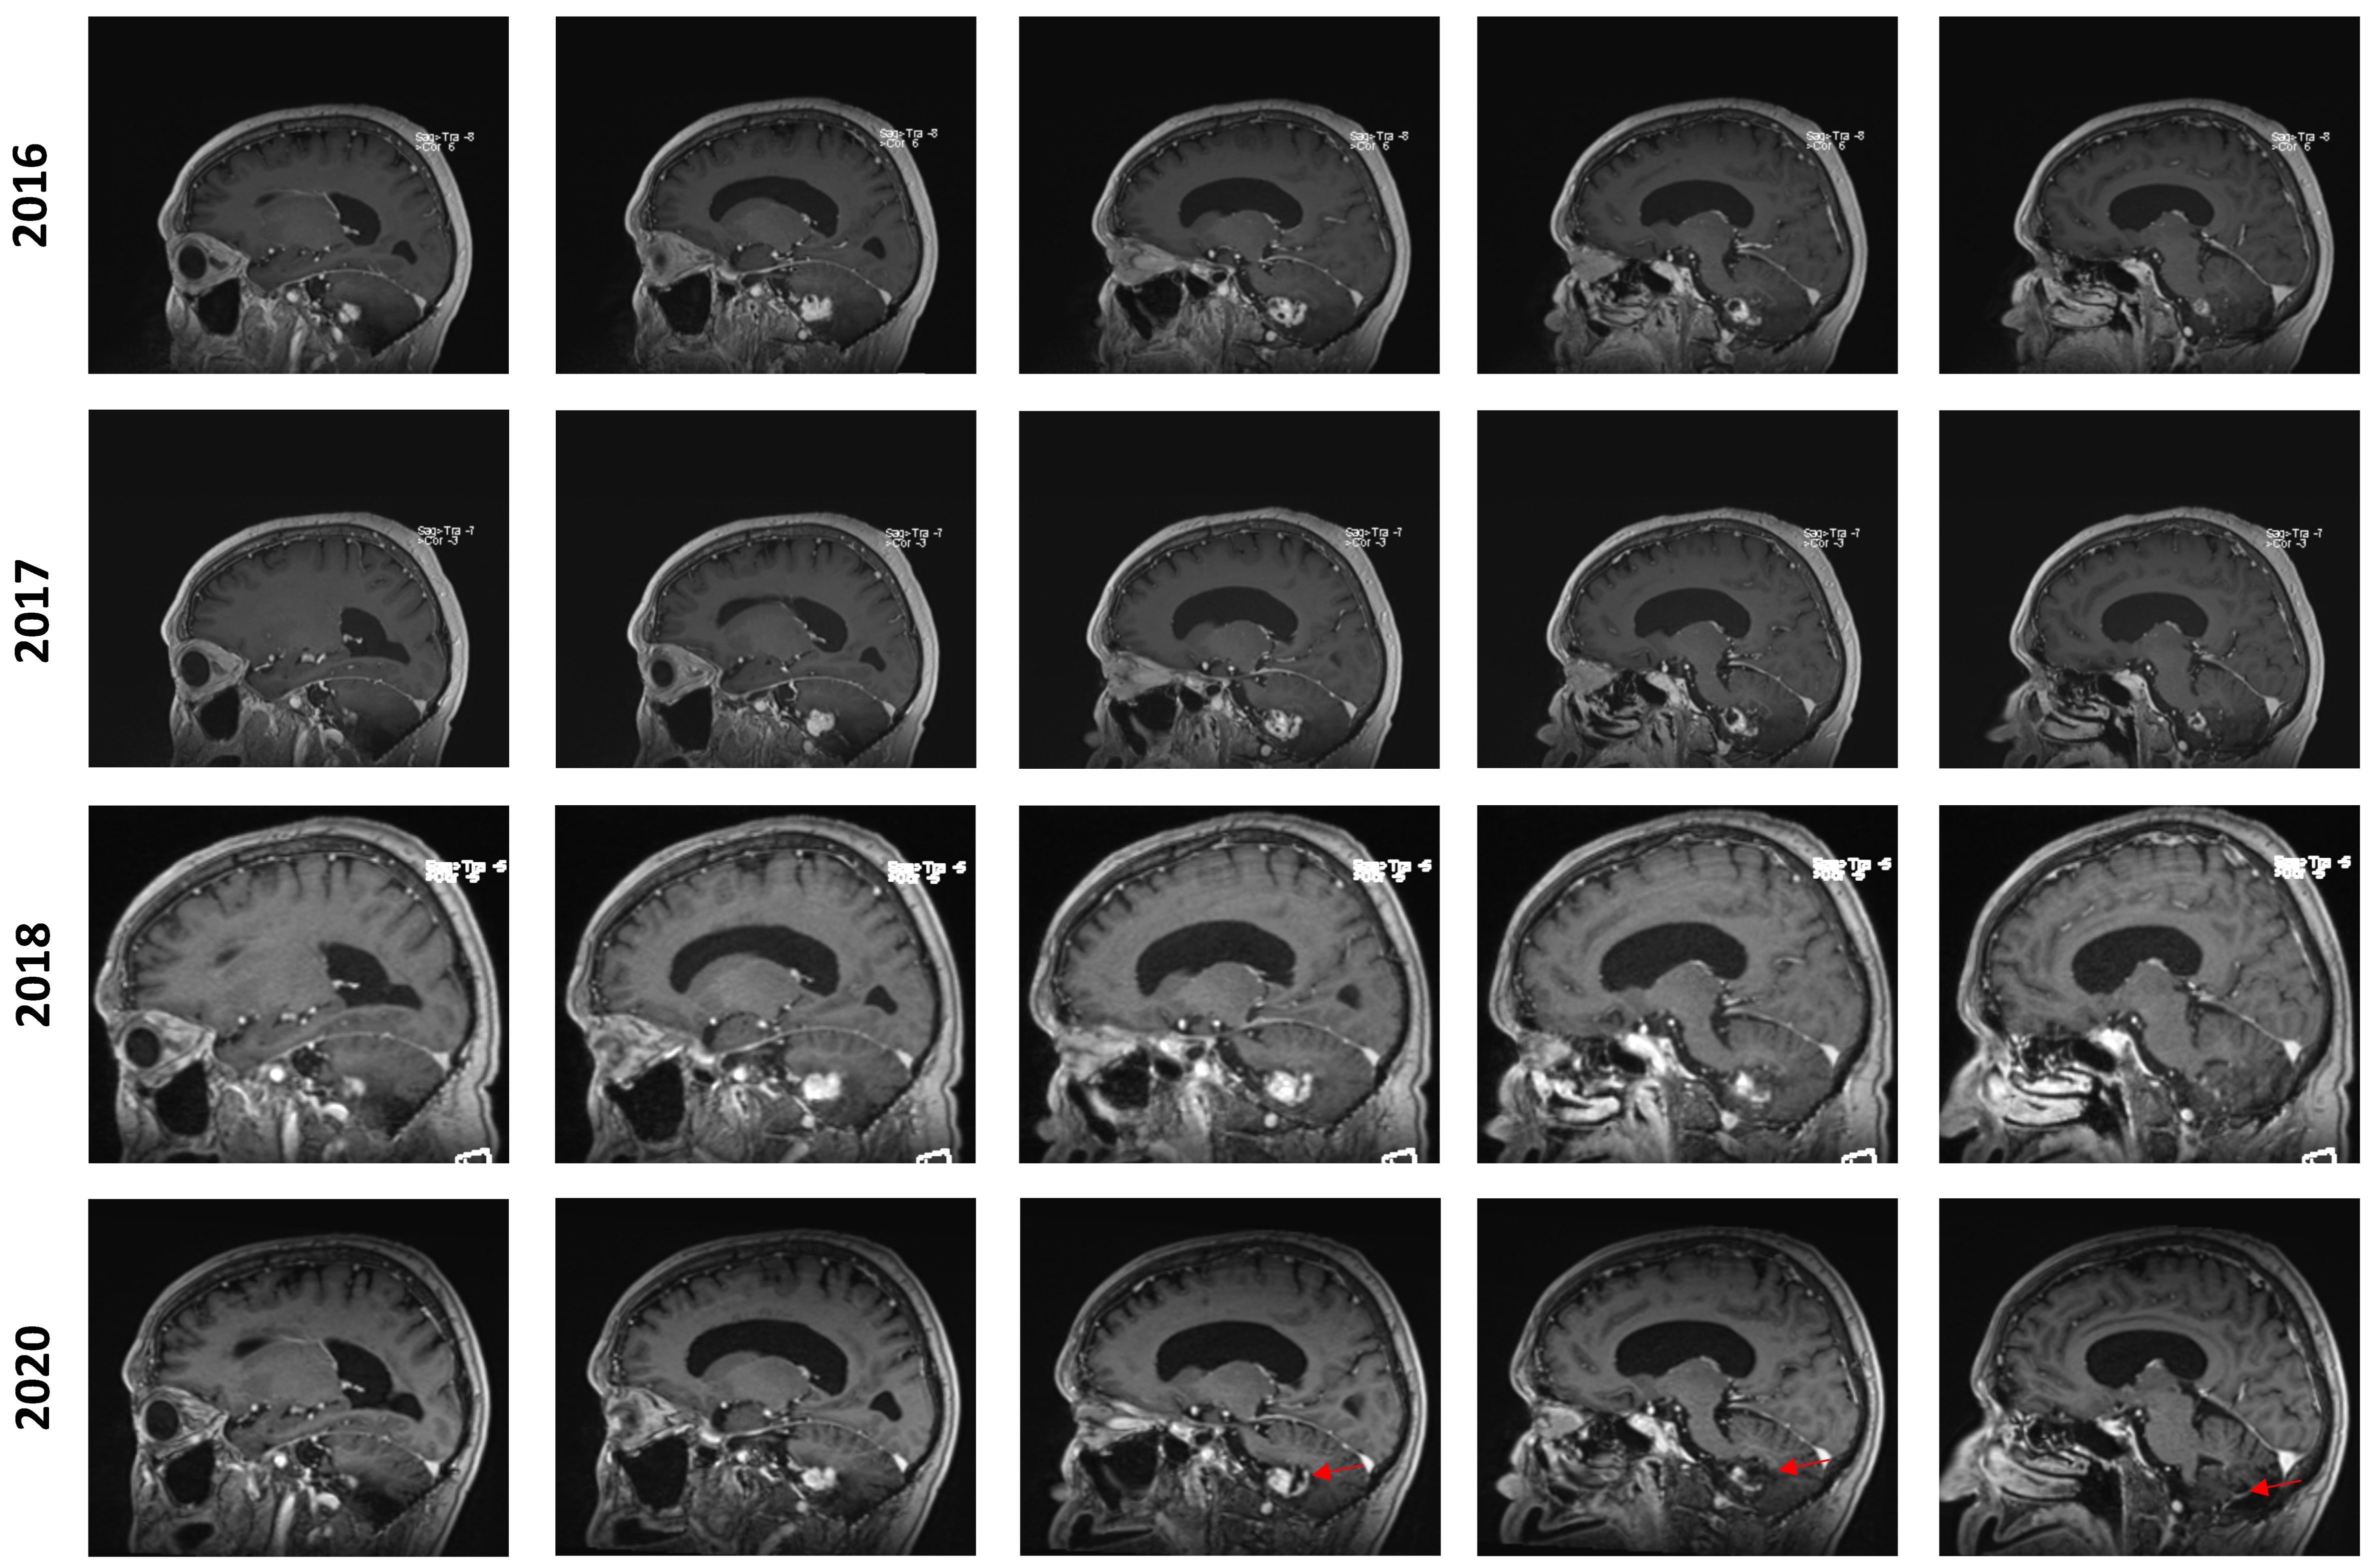

In July 2016, an MRI showed a mild increase in the lesion’s size from 24 × 17 × 17 mm to 26 × 20 × 17 mm (AP, T, CC, respectively). In the yearly imaging follow-ups, the lesion was found to be slowly shrinking, reaching a size of 18 × 13 × 14 mm in September 2020. However, at this time, the lesion still displayed a prominent cystic component that appeared to be slightly progressive. In retrospect, it appears that the solid component of the lesion remained stable while the cystic component was discreetly progressing, especially from 2018 to 2020 (Figure 2). No new lesions were found during the clinical course of the patient.

Figure 2.

Longitudinal follow-up. Representative capture of sagittal T1-weighted MRI control imaging. The date of imaging is represented. Images are organized left to right and represent a left–right progression in the sagittal plane. The red marker highlights the appearance of an enlarging cystic component in the posterior aspect of the lesion in 2020.